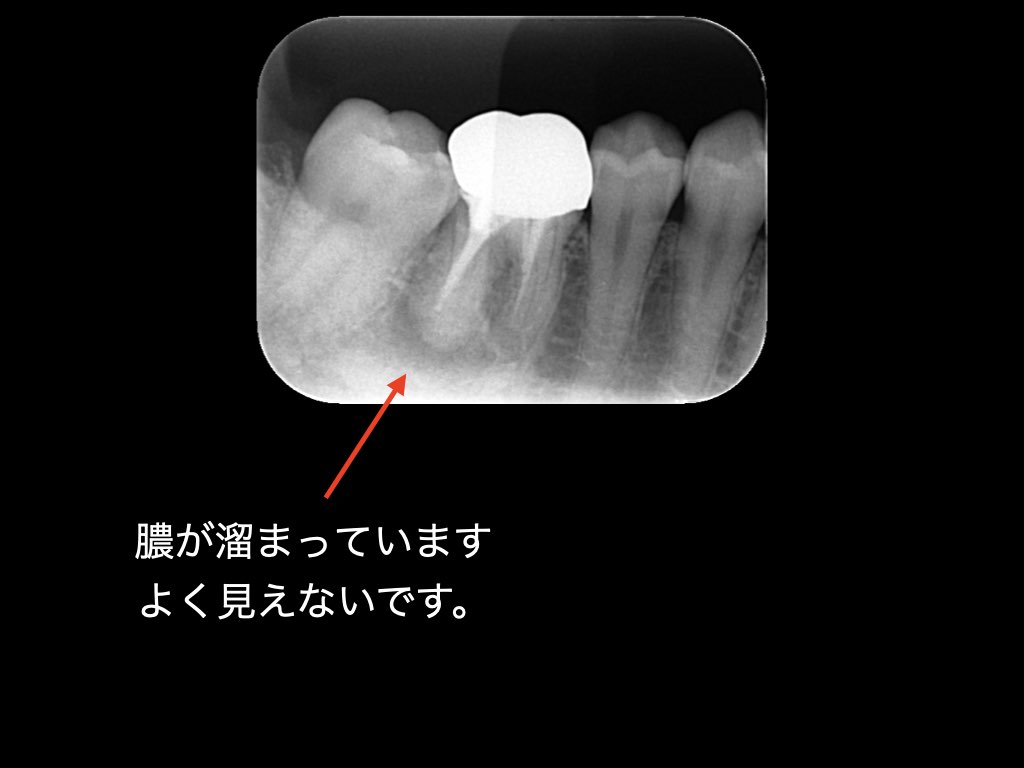

術前のレントゲンを見てみましょう。

すでに神経の処置がされてあります。下顎は骨が分厚いため、はっきりと病変が見えないことがあります。